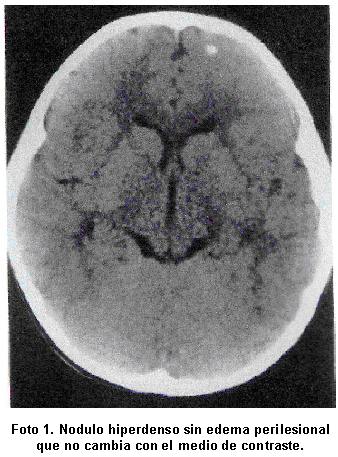

En el Cuadro 3 se describen las lesiones parasitarias halladas en los estudios de neuroimagen, que se localizaron en el lóbulo frontal (Foto 1) y (Foto 2). La TAC evidenció lesiones en cuatro pacientes y sólo en un caso se requirió la RMN para detectar lesión estructural (Foto 3). La tomografía de control reveló lesiones calcificadas en 4 pacientes (80%) y resultó normal en un caso. El estudio electroencefalográfico mostró ondas lentas focales de localización temporo-occipital bilateral en una paciente. La prueba de ELISA fue negativa en todos los casos.